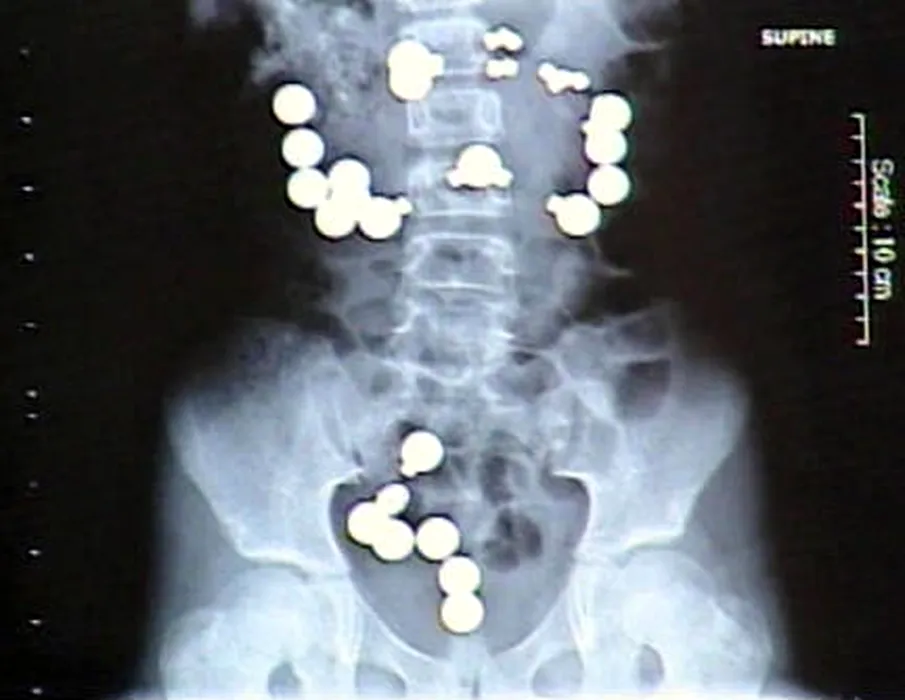

Cele mai ciudate lucruri pe care doctorii le-au găsit în stomacul pacienților. GALERIE FOTO